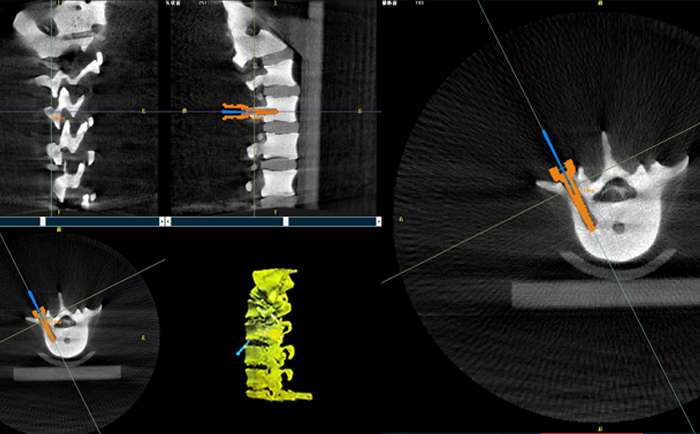

以椎弓根螺釘置入手術為例,傳統(tǒng)手術為了準確定位,需要將其多次進出反復選擇,增加了神經(jīng)損傷與螺釘損壞的風險。但外科手術機器人可通過術前規(guī)劃把手術入路、方向、釘子深度都規(guī)劃好,基本做到一步到位,讓手術更加安全。

手術開始前,外科手術機器人與3D C形臂對患者的患處進行了一次掃描,做到“知己知彼”;接著電腦系統(tǒng)為每一顆螺釘設計出前進的路徑;隨后,“穩(wěn)如泰山”的機器人之手——機械臂,開始為每條路徑掃除障礙,猶如鋪設火車軌道;最后沿標準路徑置入螺釘,猶如火車行駛在車軌之上,最終準確置入螺釘。

普愛醫(yī)療的外科手術機器人經(jīng)國家藥監(jiān)局批準,作為第三類醫(yī)療器械開始上市并應用于臨床,主要用于椎弓根螺釘內固定術、經(jīng)皮穿刺椎體成形術等術式(包括頸椎、腰椎、胸椎等)等脊柱外科手術。輔助準確定位植入物或手術器械,精度達到亞毫米級,尤其對微創(chuàng)手術、高風險手術具有明顯優(yōu)勢,可有效降低手術風險、減少手術并發(fā)癥。